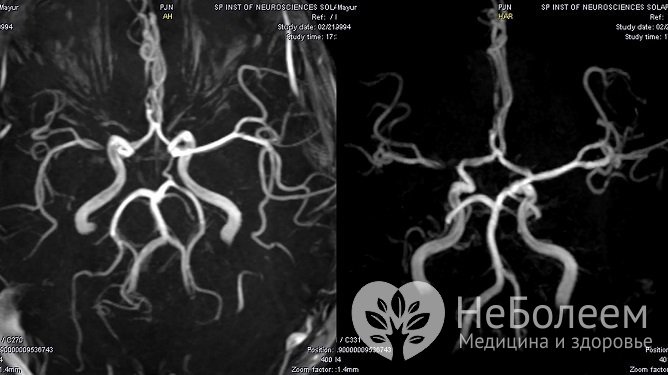

По показаниям проводится ангиография мозговых артерий.

Для диагностики водянки головного мозга может проводиться ангиография мозговых артерийПри скрининговом обследовании детей до года широко практикуется нейросонография – УЗИ черепа через открытый родничок. Выявление аномалий служит основанием для направления ребенка на МРТ.